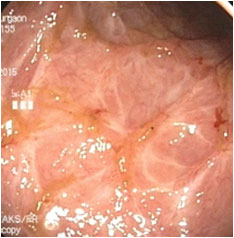

Although the pathogenesis of ulcerative colitis (UC) is unclear, one hypothesis attributes the etiology and persistence of the inflammatory process to intestinal dysbiosis. In patients with UC, dysbiosis in UC has been consistently demonstrated with a decrease in Firmicutes and Bacteroides and an increase in Proteobacteria and Actinobacteria as compared to healthy population. Successful use of FMT for UC was first reported by Bennet in 1989 when he documented reversal of his own colitis following retention enemas from a healthy donor. Suffering from steroid dependent UC of 7 years he was asymptomatic without medication three months post FMT and colon biopsy revealed no active inflammation. In 2003, Borody et al from Sydney reported 6 patients with UC of less than 5 years duration, all of whom achieved drug-free remission 4 months following weekly FMT enema for 5 weeks. Four Randomized Control Trials on FMT for UC and a recent Systematic Review have shown significant response. Although no serious adverse events were reported, some patients experienced fever, chills, bloating, flatulence, vomiting, diarrhea, and abdominal tenderness. The adverse events were more likely with Nasogastric route of administration for FMT. Flares of UC following FMT were also described. We carried out the first successful FMT for UC in India on 14th November 2014 and the patient continues to do well on maintenance FMT without use of Corticosteroids or Azathiprine. We have successfully carried out Colonoscopic FMT in several patients from 7 states from India and 3 countries with a success rate of 60%. There have been no adverse effects.